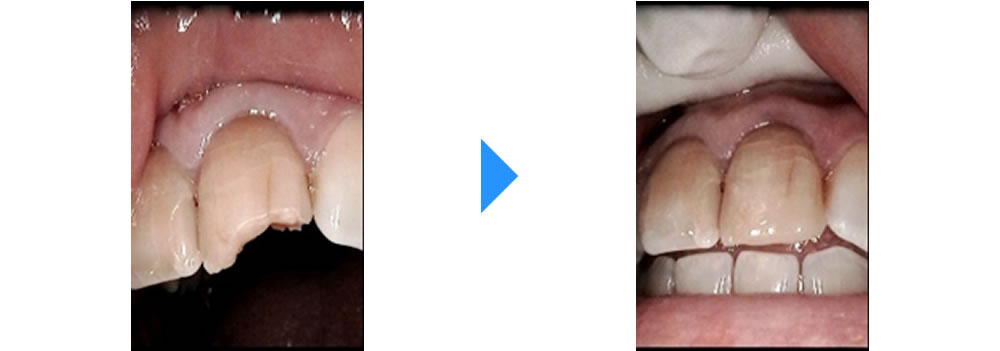

転倒して欠けた前歯をセラミッククラウンで修復した症例

転倒して欠けた前歯をセラミッククラウンで修復した症例 こちらの患者さまは「転んで前歯が欠けた」を主訴に来院されました。 前歯ということもあり、この日はCRにて応急処置をしました。後日、トリートメントコーディネーターとの時 […]